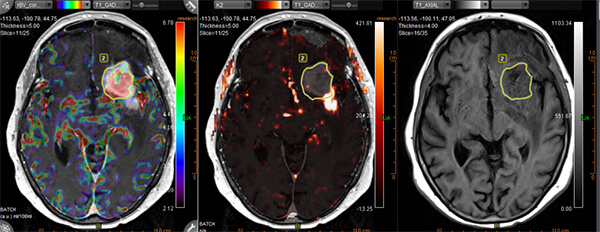

- Ειδικές τεχνικές state-of-the-art (Λειτουργική / Πολυπαραμετρική MRI, Φασματοσκοπία, Δεσμιδογραφία, Δυναμικές Αγγειογραφίες, Νευρογράφημα, Μελέτη Ροής ΕΝΥ)

- Συνδυασμός των ειδικών τεχνικών με ανατομικές εικόνες υψηλής ευκρίνειας, ο οποίος δίνει σημαντικές επιπρόσθετες πληροφορίες για τον χαρακτηρισμό του ιστού (αριθμό των κυττάρων, αιματική ροή και μεταβολική δραστηριότητα)

- Perfusion (τεχνικές DSC, DCE, ALS)